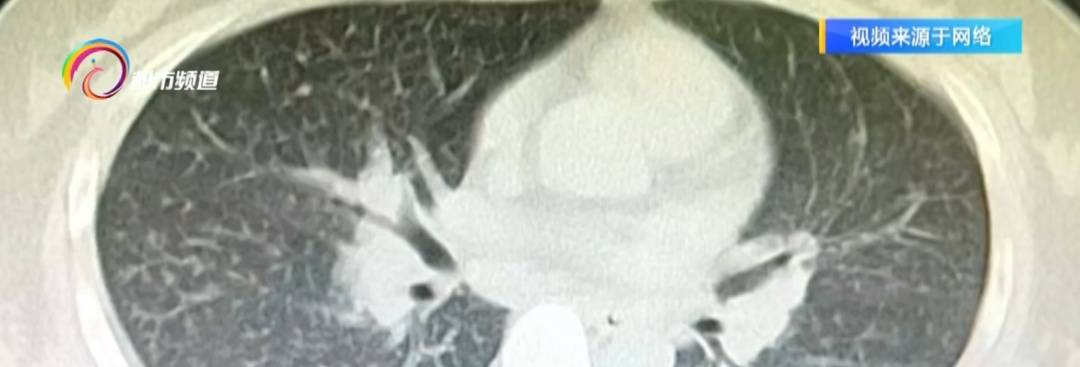

医院确诊为(wei)

急性嗜酸性粒细胞肺炎。

医生(sheng)介绍,84消毒液的核心成分是次氯酸钠。当挥(hui)发、遇酸或一(yi)些(xie)有机物时,可能释放出氯气等刺激性气体。如(ru)果只(zhi)是偶(ou)尔、低浓度(du)接触,可能会(hui)出现喉咙干痒(yang)、咳嗽(sou)、眼睛发酸、皮肤刺痒(yang)的情况,通常(chang)停止接触后可逐渐好转。但如(ru)果频繁在密闭房间里用高(gao)浓度(du)84消毒液消杀,氯气会(hui)慢慢腐蚀(shi)呼吸道和肺部,可能引(yin)发化学(xue)性支气管炎、罕(han)见类型的肺炎甚至(zhi)呼吸衰竭等严重并发症。

云南省第三人民医院 呼吸与危(wei)重症医学(xue)科副主任医师 汤秋恒:“氯气吸入(ru)到肺里就会(hui)引(yin)起(qi)急性的过敏性肺泡炎,它的过敏反应就会(hui)导致肺的嗜酸性粒细胞浸润,其实核心还是有毒有害的气体产生(sheng)的化学(xue)性肺炎的表现。”

云南省第三人民医院 呼吸与危(wei)重症医学(xue)科副主任医师 汤秋恒:“吸入(ru)的有毒气体的浓度(du)比(bi)较高(gao),时间比(bi)较长,也会(hui)导致间质性肺炎。一(yi)旦(dan)形成间质性肺炎,治疗起(qi)来就比(bi)较困难了,可能就是一(yi)个(ge)不可逆的情况。微生(sheng)物产生(sheng)不是一(yi)朝一(yi)夕的,一(yi)般我们三个(ge)月用含氯的消毒液清洁一(yi)次就可以了。”